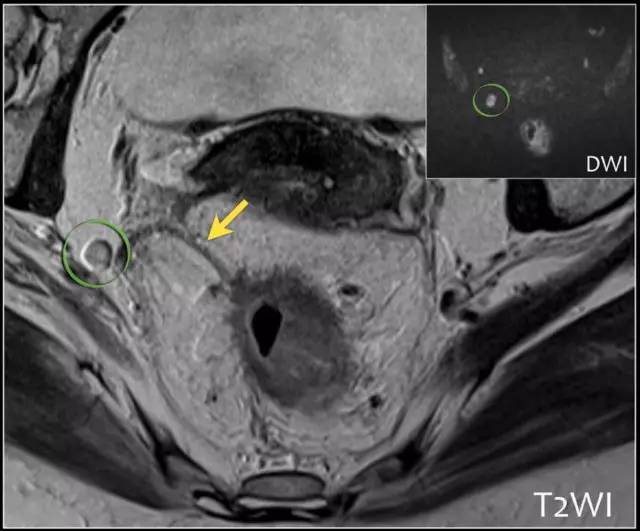

T3 分期,累及 MRF

在 T3 肿瘤的描述中,报告应包括肿瘤边缘和 MRF 之间的最短距离。MRF 阳性导致局部复发的风险增加(当肿瘤边缘和 MRF 之间的距离小于 1 mm 时,MRF 被认为是阳性)。

图 8 T3 直肠癌 MRF+

图 28 CRM 阳性的示意图(影像环周切缘的 4 个因素)。A:淋巴结;B:原发病灶;C:壁外浸润 EMVI;D:肿瘤沉积

图 29 轴向 T2 加权图像报告 CRM 的距离。虚线描绘了直肠系膜筋膜,这是 T3a 肿瘤的 CRM,预测 CRM 阴性

图 30 轴向 T2 加权图像报告 CRM 的距离。T3a 肿瘤远离直肠系膜筋膜(黑色箭头),但直肠系膜筋膜上的可疑淋巴结(白色箭头)提高了 CRM 阳性(CRM = 0 mm)的可能性。

图 31 轴向 T2 加权图像报告 CRM 的距离。T3d 肿瘤局限于固有肌层内,肿瘤毗邻直肠系膜筋膜(箭头;肿瘤为 T2)。侵犯边界似乎是左后方(白色箭头),肿瘤的 CRM 评估为 5 mm。但有两个混合信号强度淋巴结(黑色箭头)邻接直肠,导致 CRM 为 0 mm。

图 32 轴向 T2 加权图像报告 CRM 的距离。T3c 肿瘤,靠近腹膜的 EMVI(白色箭头)和不规则信号强度淋巴结的 T3c 肿瘤,通过毗邻直肠系膜筋膜的淋巴结包膜(黑色箭头)肿瘤扩展(预测 CRM = 0 mm)。